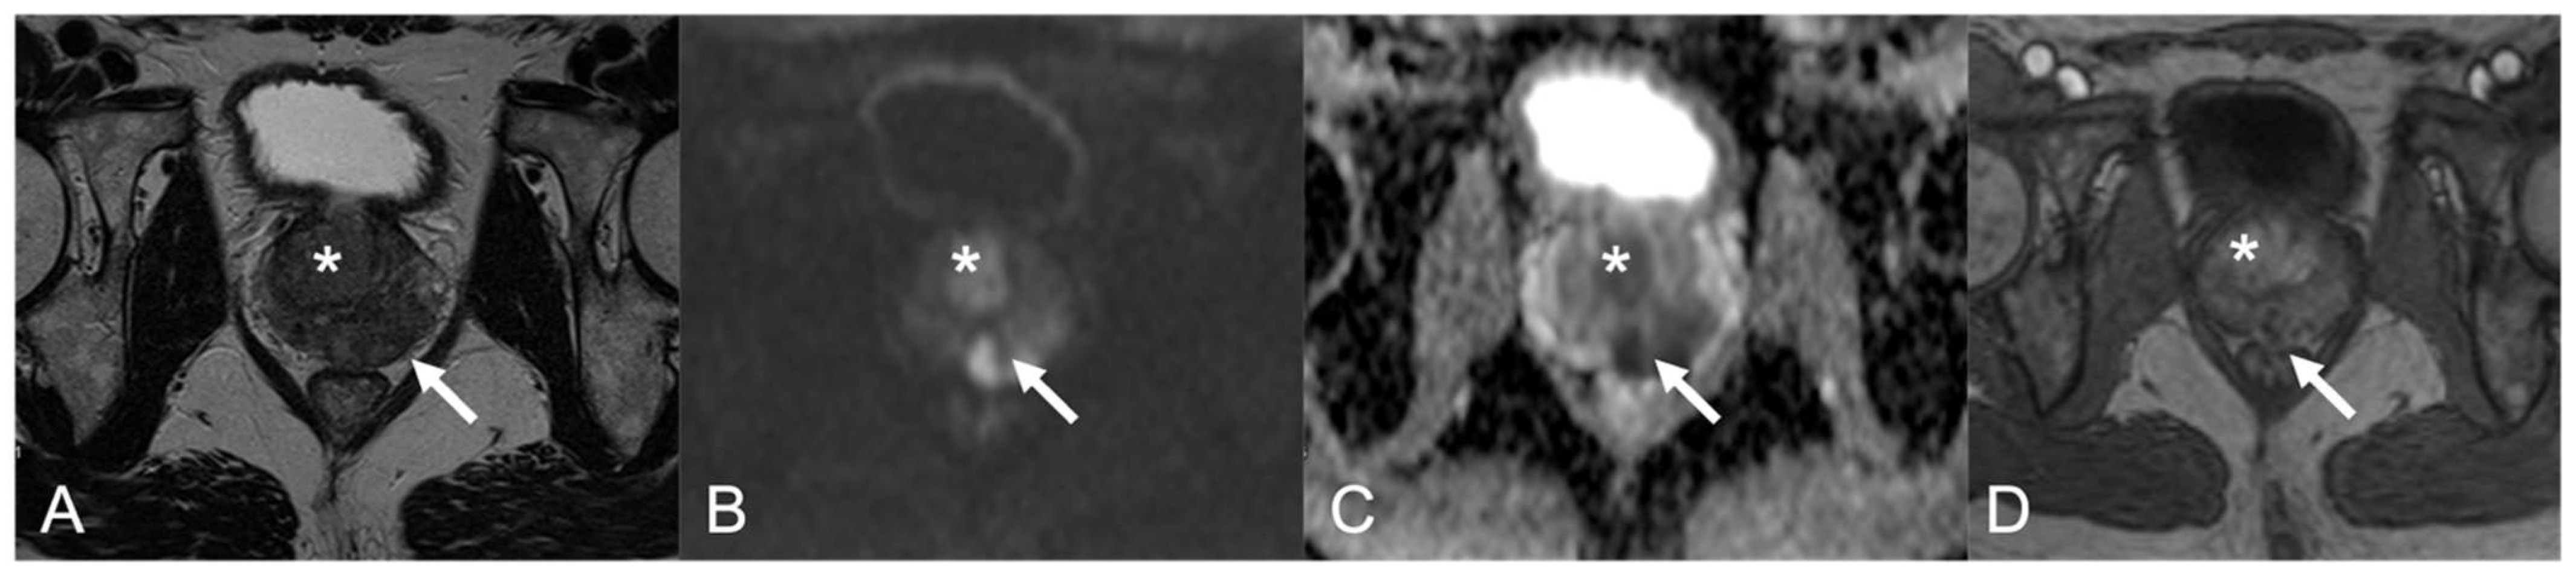

| 3 | PZ and TZ diffuse | Diffuse, inhomogeneous hypointensity, poor differentiation between PZ and TZ, glandular capsule preserved | Marked hyperintensity | Marked low ADC value | Inhomogeneous hyperenhancement, high peak | 5 |

| 4 | TZp mid-base right | 3.5-cm hypointense blurred nodule | Hyperintense | Marked low ADC value | Mild enhancement | 5 |

| 5 | PZpl mid-left; TZa mid-left | 2.8-cm hypointense area, capsular bulging; irregular, blurred marked hypointense TZ lesion | Hyperintense; hyperintense | Marked low ADC value; Marked low ADC value | Early and prolonged enhancement, high peak | 5; 5 |